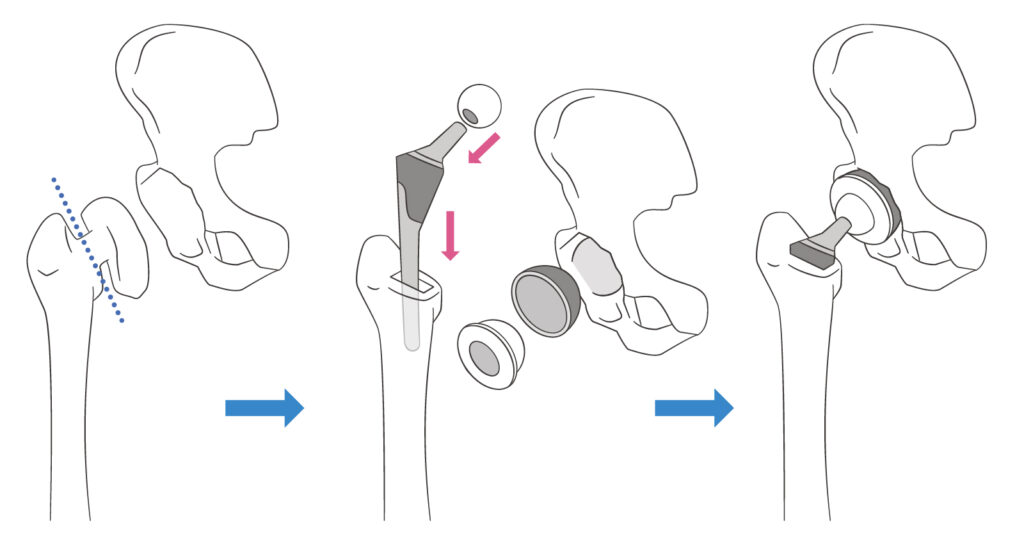

人工股関節置換術とは?

変形性股関節症などの疾患により、股関節が変形・摩耗し強い痛みがある場合に行われる手術です。

傷んだ関節を人工関節に置き換えることで、痛みが解消され、スムーズな動作を取り戻すことを目的とします。